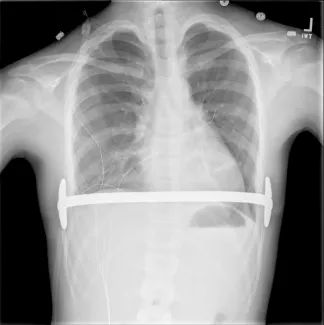

Open repair, called the Ravitch procedure, is done through a horizontal incision across the mid chest. In this repair the abnormal costal cartilages are removed, preserving the lining of cartilage, thus allowing the sternum to move forward in a more normal position. This procedure takes approximately 4–6 hours. In certain patients, an osteotomy (a break) in the sternum is done to allow the sternum to be positioned forward. In addition, to keep the sternum elevated in the desired position after the removal of the cartilages and the osteotomy, a temporary metal chest strut (bar) may need to be placed.

Repair with a metal pectus bar, called the Nuss Procedure, is achieved by bending a stainless bar to fit the chest wall. The bar is then inserted and secured through a small incision under each arm using the aid of a endoscope to monitor and avoid injury to the heart during insertion. The bar goes over the ribs and under the sternum, to push the sternum forward into the new position. The ends of the bar are secured to the chest wall. This procedure takes between 1–2 hours.